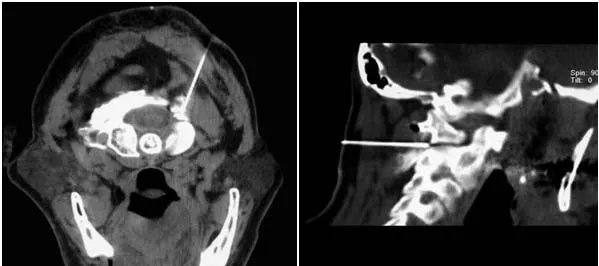

К нерву подводится медикаментозная смесь, состоящая из местного анестетика (обезболивающего препарата: лидокаин, маркаин и др.) и кортикостероида – препарата, обладающего выраженным противовоспалительным действием. Лучше всего проводить блокаду в месте прохождения нерва рядом с межпозвонковым суставом С1-2. Это позволит не только заблокировать нерв, но и оказать лечебное воздействие на данный сустав и околосуставные ткани. Выполнить блокаду можно ориентируясь на определяемые путем прощупывания анатомические структуры. Однако для увеличения эффективности процедуры и снижения рисков лучше использовать различные методы визуального контроля: ультразвук, цифровую рентгеновскую флюороскопию или компьютерную томографию.

В клинике «Оберіг» возможно выполнение данной блокады с использованием всех перечисленных способов контроля. Наиболее предпочтительной является блокада под контролем МСКТ (мультисрезовой спиральной компьютерной томографии). Используя МСКТ, врач подводит кончик иглы прямо к большому затылочному нерву, что значительно повышает эффективность процедуры. При этом четко визуализируются другие нервные и сосудистые образования шеи (например, позвоночные артерии). Это позволяет избежать их травматизации и, таким образом, максимально снизить риски для пациента.